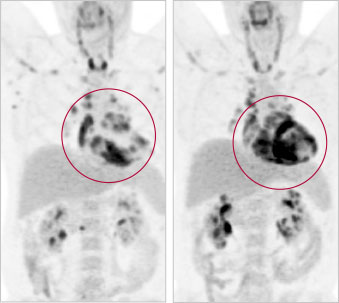

« Avec la TEP [tomographie par émission de positons] et l’IRM [imagerie par résonnance magnétique], nous pouvons maintenant diagnostiquer la maladie chez les patients qui en sont atteints, explique le Dr Beanlands. Nous cherchons à savoir quelles caractéristiques permettent de prédire qu’une personne verra son état s’aggraver et aura besoin de traitements en nous fondant sur le degré d’inflammation dans le cœur. »

3. Évaluer et améliorer l’utilisation des techniques d’imagerie de pointe, comme la TEP et l’IRM, afin de mieux diagnostiquer et surveiller la sarcoïdose cardiaque.